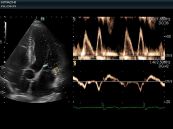

Những hình ảnh và các phép đo thêm được quyết định bởi lý do cho sự yêu cầu hoặc để nghiên cứu ban đầu và được thảo luận trong mỗi mặt cắt. Tham khảo bài viết dưới đây để biết thêm về Tiêu chuẩn mục kết quả tối thiểu siêu âm tim nhé!

Siêu âm tim là một trong những phương pháp an toàn và hiệu quả để kiểm tra tình trạng tim mạch của bản thân. Việc siêu âm tim cần được thực hiện định kỳ hằng năm để chắc chắn rằng các bạn vẫn luôn duy trì một trái tim khỏe mạnh. Cùng eLip tìm hiểu ý nghĩa của các ký hiệu thường dùng trong siêu âm tim ngay nhé!

Báo cáo kết quả siêu âm tim phải bao gồm Doppler và M-mode hoặc số đo trên 2D, mô tả hình ảnh quan sát và một kết luận ngắn. Tham khảo bài viết ngay dưới đây để biết thêm về cách thức trả lời kết quả siêu âm tim nhé!